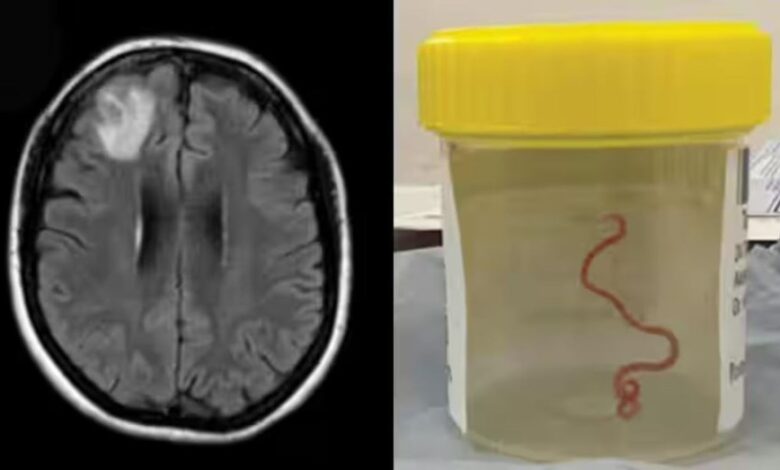

Desconcertados, los médicos realizaron una resonancia magnética a una mujer australiana de 64 años después de que comenzara a sufrir lapsos de memoria y notaron una «lesión atípica» en el frente de su cerebro.

Era una lombriz de ocho centímetros llamada Ophidascaris robertsi, que según investigadores son parásitos comunes en canguros y pitones diamantina pero no en humanos.